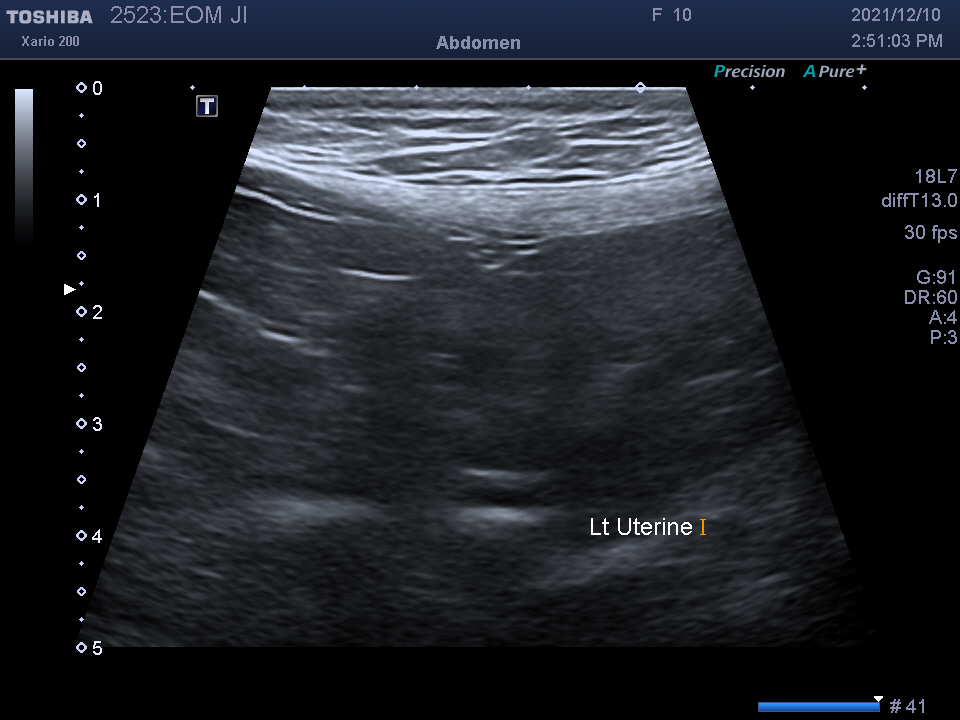

복강 내 장기를 자세히 알 수 있는

복부 초음파 검사를 진행하였습니다.

검사 결과를 종합하여 자궁 축농증이라는 진단을 받았습니다.